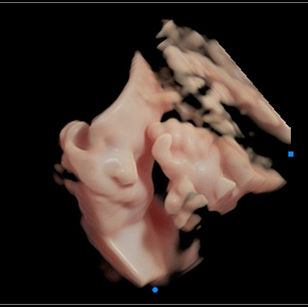

32 Weeks Pregnant

At 32 weeks pregnant, your baby is well into the third trimester and making big strides in growth and maturity. They’re starting to look more like a full-term newborn, but still need more time for their brain, lungs, and fat stores to fully develop.

Bones: Fully formed but soft and flexible; skull bones remain unfused for easier passage through the birth canal.

Muscles: Getting stronger, and movements may feel more forceful.

Skin: Less wrinkled as fat builds up, giving baby a rounder appearance.